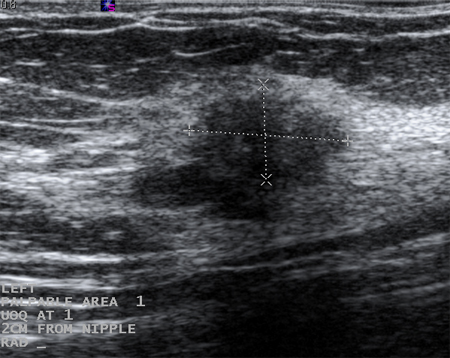

Os cistos que persistem ou não se resolvem completamente com a aspiração devem ser submetidos a biópsia para descartar a malignidade. Da mesma forma, a biópsia deve ser considerada em cistos complexos ou naqueles com elementos sólidos. As características sonográficas podem classificar uma massa sólida tanto como "provavelmente benigna" quanto como "suspeita". Massas lisas, ovais, lobuladas, com margens claramente definidas e mais largas que compridas geralmente são benignas (por exemplo, fibroadenoma). Se a massa é irregular, heterogênea, tem margens espiculadas ou pouco definidas, é mais comprida que larga, ela é considerada "suspeita" para malignidade, e deve ser realizada uma biópsia.[Figure caption and citation for the preceding image starts]: Imagem ultrassonográfica de um carcinoma complexoCortesia do Dr. Lane Roland, Universidade de Louisville; usado com permissão [Citation ends].

[Figure caption and citation for the preceding image starts]: Imagem ultrassonográfica de fibroadenomaCortesia do Dr. Lane Roland, Universidade de Louisville; usado com permissão [Citation ends].